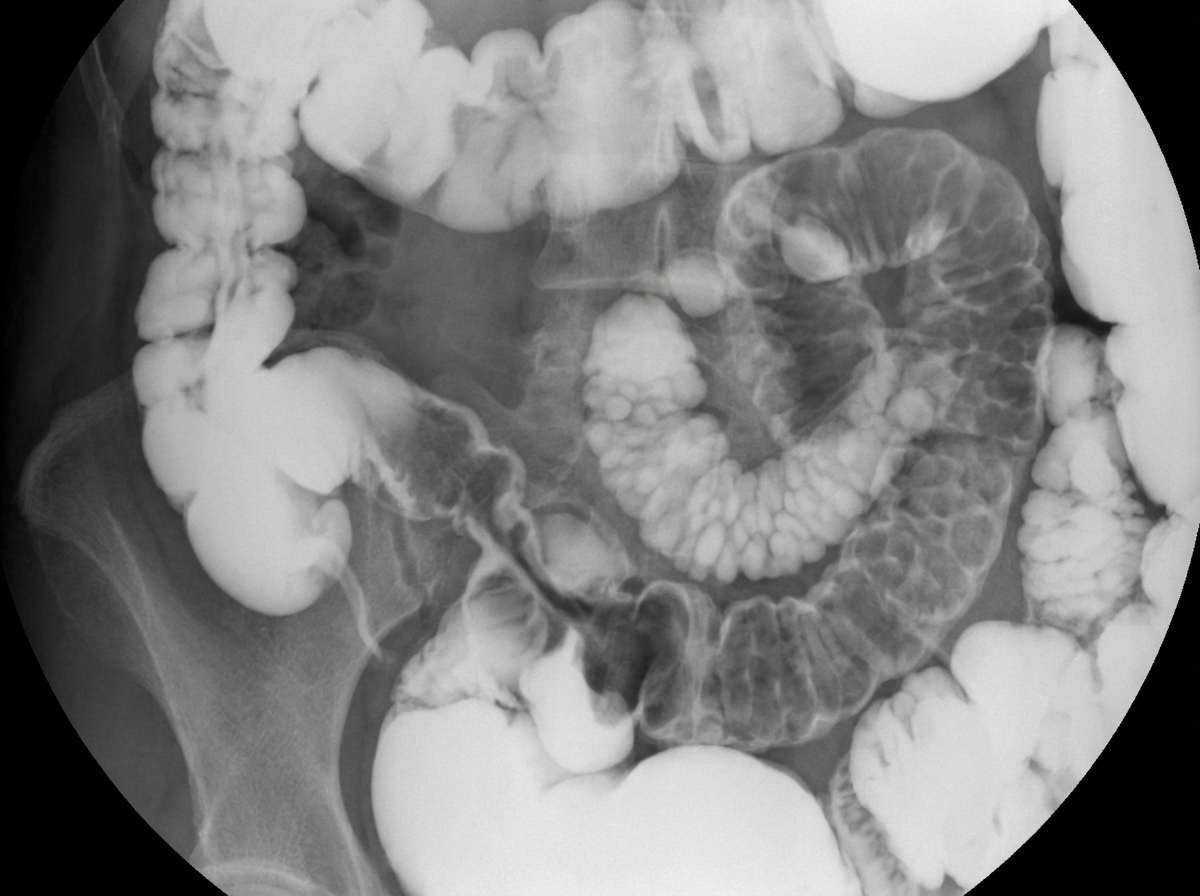

What is the most probable diagnosis on this barium film?

Explanation: ***Crohn's disease*** - Characteristic **string sign of Kantor** (narrowed terminal ileum) and **skip lesions** with normal bowel segments between diseased areas are pathognomonic on barium studies. - **Cobblestone mucosa** appearance and **rose-thorn ulcers** create a distinctive pattern that differentiates it from other inflammatory conditions. *Lymphoma* - Typically shows **smooth, regular narrowing** without the irregular ulceration and skip pattern seen in Crohn's disease. - **Polypoid masses** or **aneurysmal dilatation** are more characteristic features on barium studies, not the string sign. *Brucellosis* - Rarely causes significant **small bowel involvement** that would be visible on barium studies. - When GI symptoms occur, they are usually **non-specific** without the characteristic radiological findings like skip lesions or string sign. *Tuberculosis* - Shows **concentric narrowing** of the ileocecal region with **shortened cecum** and **gaping ileocecal valve**. - Lacks the **skip lesions** and **cobblestone appearance** characteristic of Crohn's disease on barium studies.